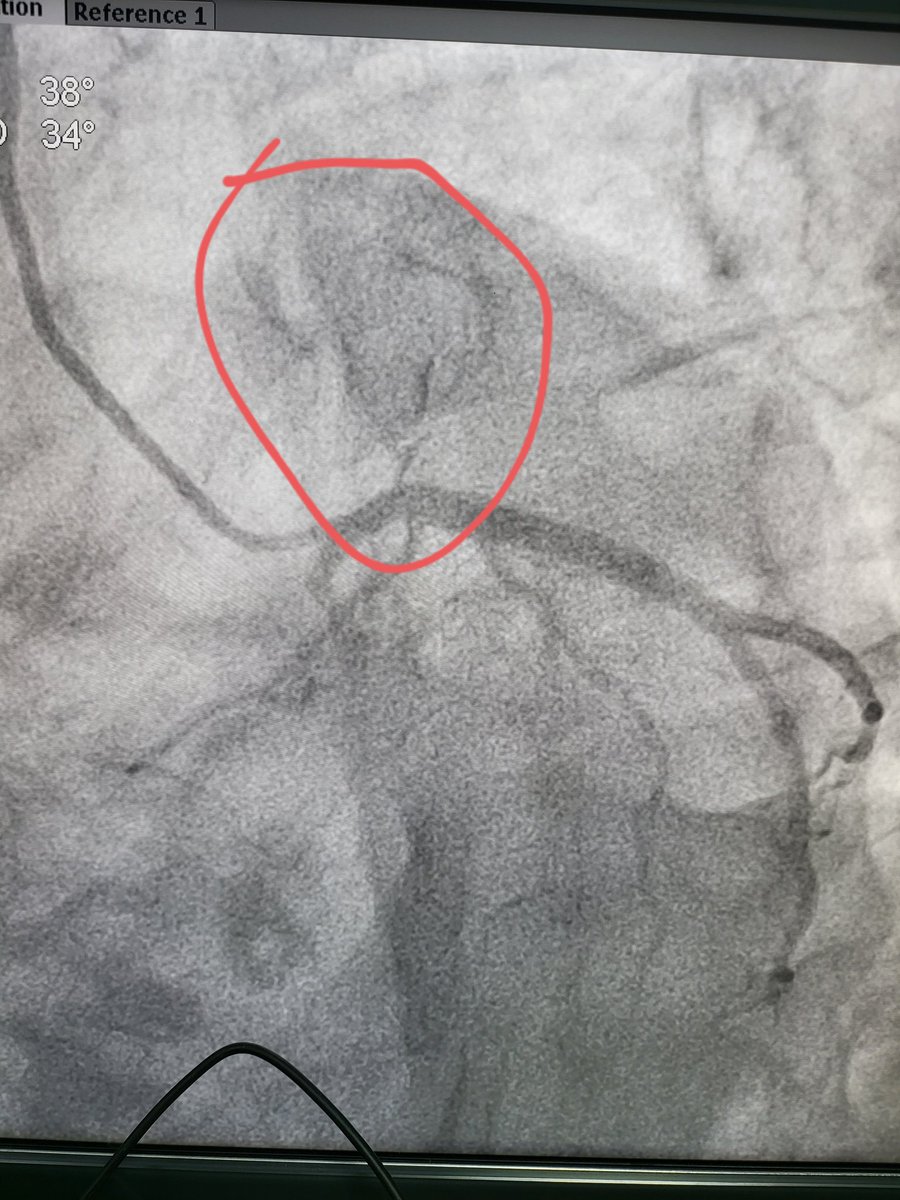

Angio - LAD 100% blocked